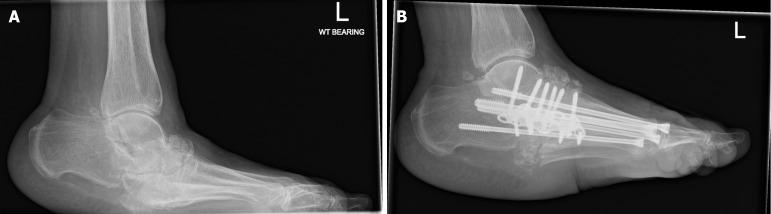

The prevalence of diabetes mellitus and its associated complications, particularly diabetic foot pathologies, poses significant healthcare challenges and economic burdens globally. This review synthesises current evidence on the surgical management of the diabetic foot, focusing on the interplay between neuropathy, ischemia, and infection that commonly culminates in ulcers, infections, and, in severe cases, amputations. The escalating incidence of diabetes mellitus underscores the urgency for effective management strategies, as diabetic foot complications are a leading cause of hospital admissions among diabetic patients, significantly impacting morbidity and mortality rates. This review explores the pathophysiological mechanisms underlying diabetic foot complications and further examines diabetic foot ulcers, infections, and skeletal pathologies such as Charcot arthropathy, emphasising the critical role of early diagnosis, comprehensive management strategies, and interdisciplinary care in mitigating adverse outcomes. In addressing surgical interventions, this review evaluates conservative surgeries, amputations, and reconstructive procedures, highlighting the importance of tailored approaches based on individual patient profiles and the specific characteristics of foot pathologies. The integration of advanced diagnostic tools, novel surgical techniques, and postoperative care, including offloading and infection control, are discussed in the context of optimising healing and preserving limb function.

糖尿病及其相关并发症,尤其是糖尿病足病变的患病率,在全球范围内构成了重大的医疗挑战和经济负担。本综述综合了关于糖尿病足手术治疗的现有证据,重点关注神经病变、缺血和感染之间的相互作用,这些因素通常最终导致溃疡、感染,严重时还会导致截肢。糖尿病发病率的不断上升凸显了有效管理策略的紧迫性,因为糖尿病足并发症是糖尿病患者住院的主要原因,对发病率和死亡率有重大影响。本综述探讨了糖尿病足并发症的病理生理机制,并进一步研究了糖尿病足溃疡、感染和夏科关节病等骨骼病变,强调了早期诊断、综合管理策略和跨学科护理在减轻不良后果方面的关键作用。在讨论手术干预措施时,本综述评估了保守手术、截肢和重建手术,强调了根据个体患者情况和足部病变的具体特征采取定制方法的重要性。在优化愈合和保留肢体功能的背景下,讨论了先进诊断工具、新型手术技术和术后护理(包括减负和感染控制)的整合。